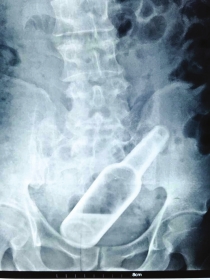

《长株潭报》通讯员梁辉摄

长株潭报株洲讯(记者杜方江通讯员梁辉)欠债没还,追债人恼羞成怒操起玻璃瓶从肛门处塞入长沙男子李钱缺(化名)体内。9月1日凌晨,他赶到湖南省人民医院急诊科就医。

50来岁的李钱缺离异多年。8月30日,他被追债人从肛门强行塞入一个装花露水的玻璃瓶。从B超和CT上可清晰看到,玻璃瓶底朝下嵌在李钱缺的直肠下段,瓶内还有小半瓶液体。结直肠肛门外科医生董宏宇表示,因异物进入体内已有2天,已造成肛门括约肌损伤和肠壁严重水肿,只能通过开腹手术将异物取出。

“我们曾经收治过塞玻璃杯、手电筒的。”董宏宇提醒,肛门被塞进异物后一定要及时就医,否则导致肠破裂大出血,将危及生命。